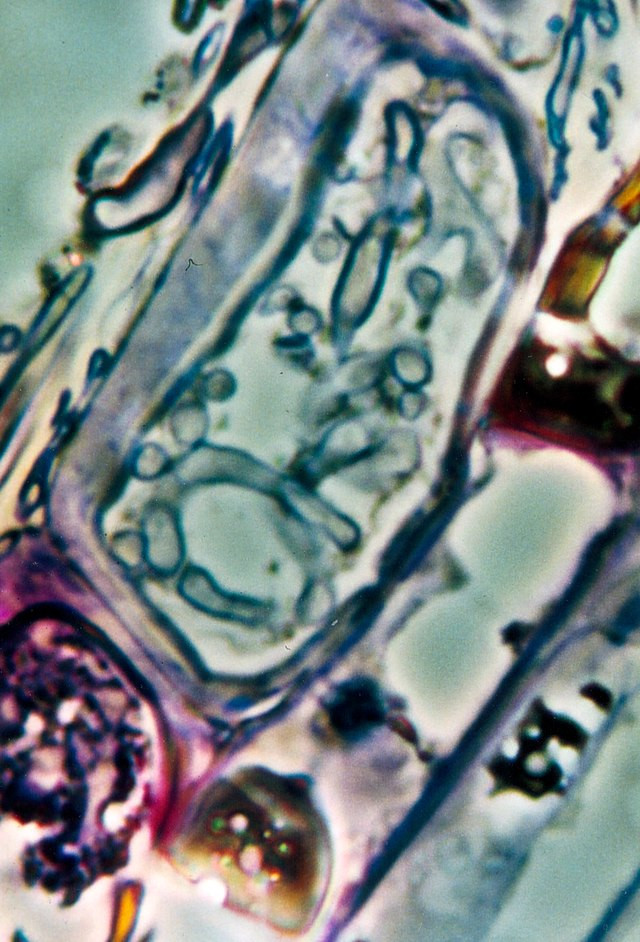

Raziskovalke in raziskovalci so dodatno preverjali prisotnost gliv v tkivnih preparatih raka trebušne slinavke, dojk, pljuč in jajčnikov ter kožnega raka s štirimi različnimi metodami barvanja. Glive, ki so jih videli na tkivnih preparatih, so večinoma rasle v rakavih ali imunskih celicah.